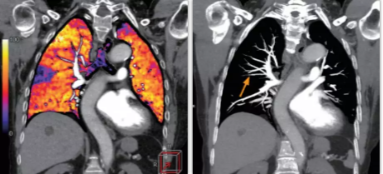

相比傳統(tǒng)成像方式,肺部柔性減影技術通過人工智能,對平掃數據和CT肺動脈血管掃描數據進行智能比對,解碼并識別各個器官(肺、氣管、肺動脈、肺靜脈、主動脈等)的空間位置,并在三維空間中進行體素級的柔性配準,從而極大提升了不同序列數據的空間位置的一致性。通過肺部柔性減影技術可得到肺強化碘圖,可以顯示出傳統(tǒng)CTPA圖像看不到的小栓塞病變,提高了栓塞檢出率,其結果甚至可與SPECT吻合。

肺智能柔性減影成像功能發(fā)現亞段肺栓塞

柔性成像功能為開拓者Ai-640CT的臨床應用帶來了很多顛覆式的拓展功能,如佳能獨有的能譜+灌注的多模態(tài)成像方案。

此次,佳能對能譜成像方案也進行了升級,結合了AI的柔性能譜技術從能譜技術的四個基本判別條件——輻射劑量,數據精度,覆蓋寬度和能量分離度著手,分別優(yōu)化了以上四種技術,實現了kV和mA的獨立切換。高低kV的切換保證了能量分離度;根據體位自動調整的mA有效降低了輻射劑量;16厘米容積探測器解決了覆蓋寬度的問題;單球管配合AI感知掃描技術與AI器官柔性配準算法,確保了數據精度。以此作為保障,佳能能譜+灌注的多模態(tài)成像方案僅需一次掃描即可同時獲得能譜數據和灌注數據。